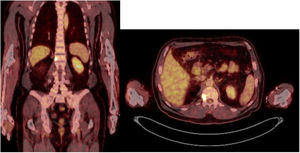

Sixty-two-year-old woman, with a history of left hemithyroidectomy due to nodular hyperplasia. Clinical symptoms began with general bone pain of 2 years onset, treated with NSAIDs. Following this, hypophosphataemia and hyperphosphaturia were found, AP of 273 U/l, severe radiographic osteopenia with vertebral T11-T12-L1-L2 fractures, with no trauma. Initially she was diagnosed with adult hypophosphoremic osteomalacia, and began medical treatment with phosphorous and calcitriol, which led to clinical improvement. After this, progressive impairment of renal function began with ongoing hypophosphataemia despite medical treatment. This led to chronic stage IV kidney disease with bilateral cortical nephrocalcinosis. Consecutively, elevation of PTH to 1.212 pg/mL, FGF23 to 415 U/l (n < 145), creatinine to 2.72 mg/dl and phosphorous to 1.7 mg/dl were detected. With these results, the octreoscan detected uptake in the right groin, with soft tissue mass at that level. After the NMR (Fig. 3) an ultrasound-guided CNB resulted in PMT. Extended resection was performed (Fig. 4) with histological confirmation of PMT, mad immediate analytical normalisation. Unfortunately this patient presented with chronic complications of hypophosphataemic rickets, SHPT and nephrocalcinosis.

The anatomical location of the tumour requires a detailed physical examination, together with imaging tests: octreoscan, PET/CT with 25-fluorodesoxyglucose and NMR.10 Also, in recent years new imaging tests have been included, such as Ga-DOTANOC PET/CT (using a modified octeotride molecule) or venous sampling with FGF23 in areas where imaging studies suggest suspicious lesions.25,10 In our centre we chose to use the octreoscan and PET/CT with 25-fluorodesoxyglucose for anatomical location of the tumour and then the NMR to identify and schedule biopsy and treatment. Even so, due to the size with which on occasions the PMT presents, it is not possible to initially detect it by these methods, and repetition of imaging tests is therefore recommended during follow-up,27 which also occured in our cases (Table 3).